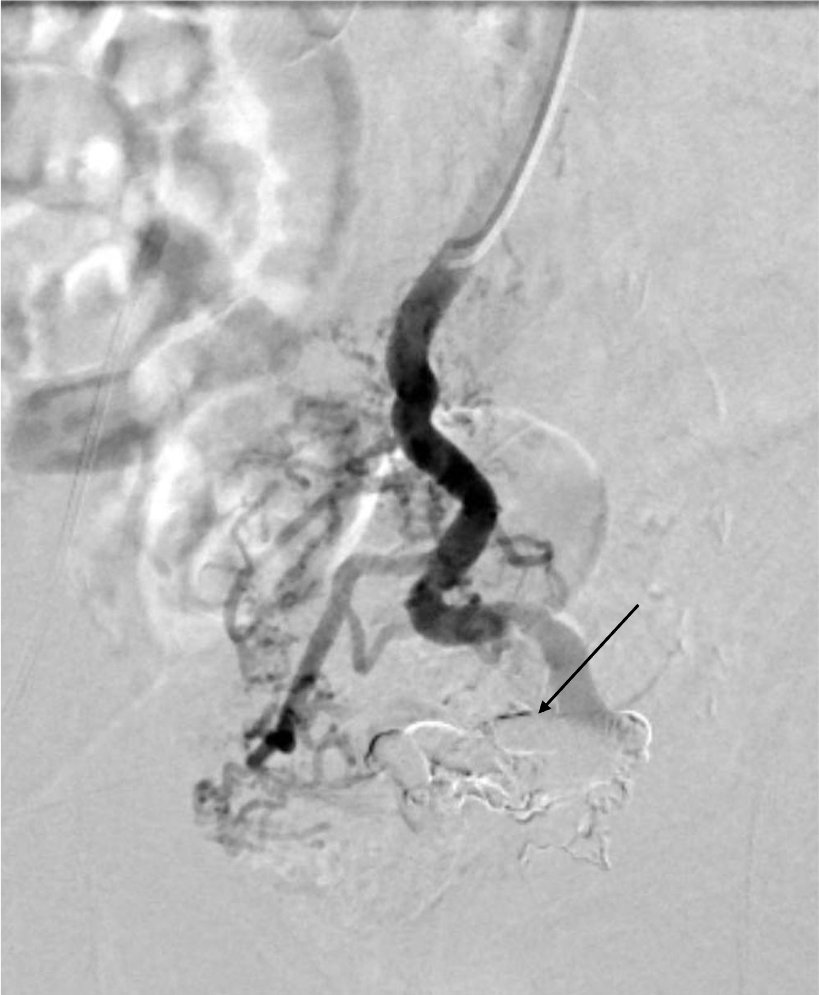

直腸静脈瘤の破裂予防目的にヒストアクリルを用いた経皮経肝的静脈瘤塞栓術を施行した。治療一か月後の治療効果判定に撮影を行った。

肝硬変のスクリーニング目的の造影CTにて直腸静脈瘤が判明した。破裂予防目的に経皮経肝的静脈瘤塞栓術を施行した。術前CTにて血管解剖を把握の上、治療を行った。術後一か月の造影CTにて、標的血管の良好な閉塞が確認された。

当該疾患の診断における造影CTの役割

直腸静脈瘤を始めとする異所性静脈瘤においては、IVR治療が選択されることが多い。術前に正確な解剖の把握が必要であり、造影CTの果たす役割は大きい。特に門脈系の良好な描出が求められ、適切な時相での撮影が肝要である。撮影後thin slice軸位断像での観察、任意多断面再構成像(MPR)やVolume rendering画像(VR)で評価を行い、術中のガイドとする。また肝細胞癌を併発することが多い為、動脈優位相における撮影も行う必要があり、dynamic studyを要する。治療においてはヒストアクリルや金属コイルなどのアーチファクト源となり得るデバイスが使用されるため、必要に応じてmetal artifact除去を活用する必要がある。また別部位に新たな静脈瘤が生じたり、腹水などの門脈圧上昇に伴う所見や門脈血栓などの合併症が生じる危険性があるため、造影CTによる評価が重要である。

CT技術や撮像プロトコル設定について

本症例においては、腎機能障害や心不全など、特段併発症を有さない患者様であったため、標準的な撮影プロトコルで撮影を施行した。管電圧は120kVを使用し、逐次近似併用(ASiRV 20%)で再構成を行った。また造影については、536mgI/kgの投与とし、固定法(動脈相 35秒、門脈相80秒後、平行相180秒後)で撮影を行った。ただし肝硬変患者においては、腎機能障害を有することがしばしばあり、その場合には造影剤減量が必要となる。従って低管電圧撮影や逐次近似再構成法、dual energy CTを使ったvirtual monochromatic imageなどを適宜活用する必要がある。また金属コイルなどによる血流改変を施行した場合には、metal artifact除去などを併用して評価を行う必要がある。加えて肝肺症候群などに起因する心機能障害を有することがあり、その場合には固定法による撮影ではなく、bolus tracking法などを活用した撮影が必要となる。